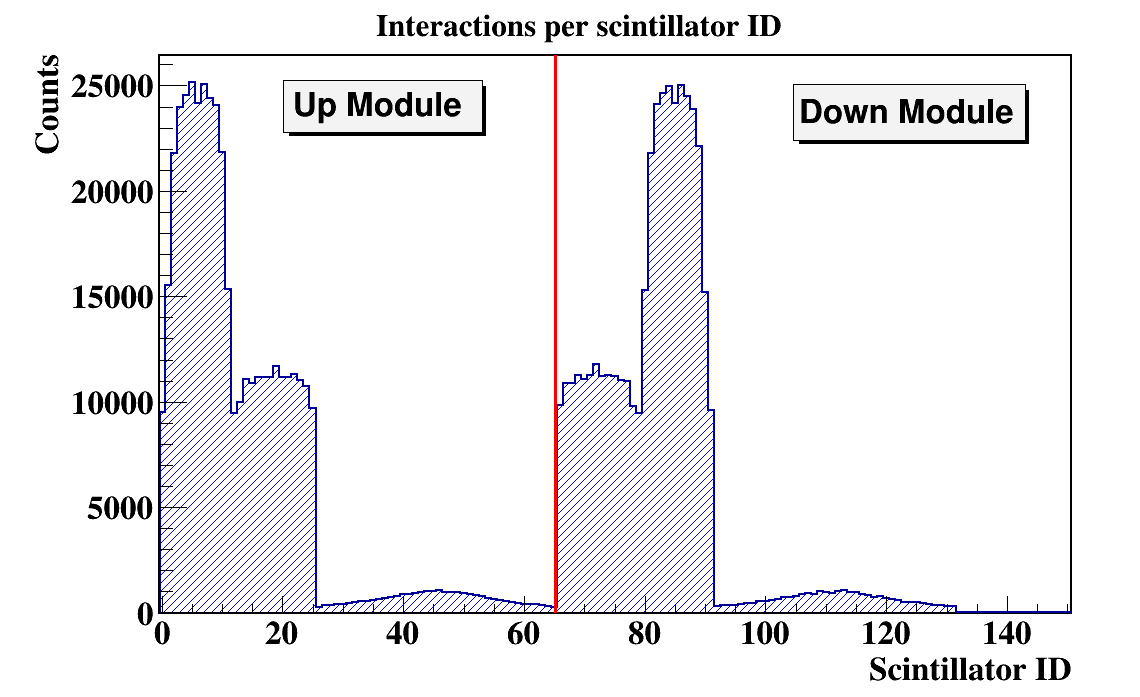

In order to quantify the J-PEM geometry we have performed Monte-Carlo simulations. The simulations were performed using the GATE package. GATE (Geant4 Application for Tomographic Emission) is a Monte Carlo simulation platform developed by the Open-GATE collaboration [40] based on Geant4 software. It is dedicated to numerical simulations in medical imaging and radiotherapy. It utilizes an easy macro mechanism to configure the experimental settings for computed tomography, single photon emission computed tomography, positron emission tomography as well as optical imaging (bioluminescence and fluorescence) or radiotherapy. In the simulations the full geometry of the J-PEM detector and the composition of the detector material were taken into account. The interactions of photons in the scintillators were simulated by GATE. In the simulations we assumed that annihilation source is placed in the center of the detector and that the back-to-back photons (each with energy of 511 keV) from the Ps annihilation are isotropically emitted. Energy deposition inside the plastic scintillator is shown in Fig.7. According to the performed simulation we are able to register 4.33% of generated back to back events. After adding the condition that both photons deposited at least 200 keV energy fraction of register annihilation drop to 0.8 % . Such a condition is needed for the suppression of the scatter fraction [41]. We found that there was 11.3% primary back-to-back registered events where at least one photon scattered in WLS.